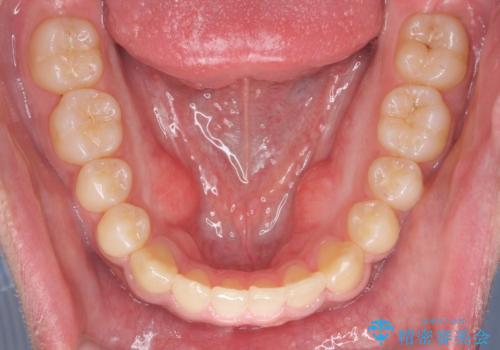

骨格性の受け口 非抜歯で下の歯を後ろに下げる インビザラインで インプラント矯正

- 受け口を主訴に来院。

他院でマウスピース矯正を始めたが、担当医に不信感をもち転院。

治療により受け口が改善し、下あごの輪郭も若干後ろに下がった印象になりました。

当院では下の歯を後ろに下げるため矯正用ミニスクリューを用いてしっかり移動を行う等ご説明をし、治療開始しました。